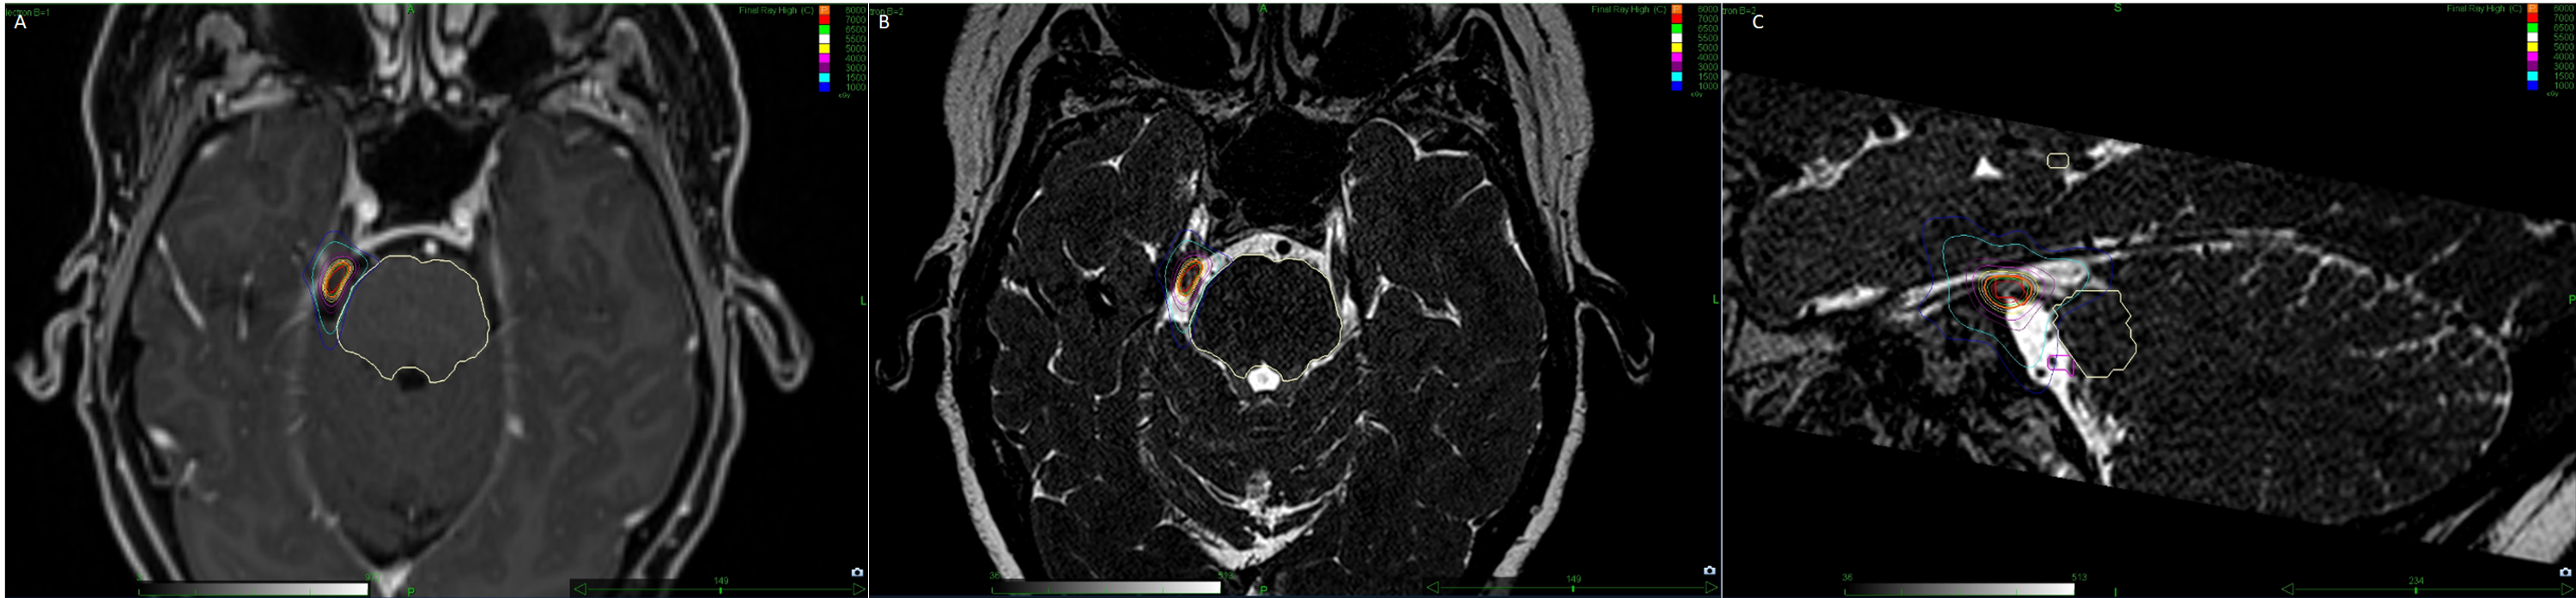

Cyberknife radiosurgery in treating trigeminal neuralgia Journal of Stereotactic Radiosurgery For Trigeminal Neuralgia Objectives the purposes of this study are to assess the effectiveness of cyberknife® stereotactic radiosurgery (srs) in. Radiosurgery was first attempted for trigeminal neuralgia in the early 1970s by lars leksell, who used the stereotactic technology. Trigeminal neuralgia is a chronic pain condition of the trigeminal nerve affecting 12 per 100,000 people. The aims of this systematic review are to. Stereotactic Radiosurgery For Trigeminal Neuralgia.

Commissioning a multileaf collimator virtual cone for the stereotactic Stereotactic Radiosurgery For Trigeminal Neuralgia Radiosurgery was first attempted for trigeminal neuralgia in the early 1970s by lars leksell, who used the stereotactic technology. Stereotactic radiosurgery is an effective treatment option for trigeminal neuralgia (tn), with frameless stereotactic radiosurgery. The aims of this systematic review are to provide an objective summary of the published literature specific to the treatment of classical trigeminal neuralgia with stereotactic. Stereotactic Radiosurgery For Trigeminal Neuralgia.